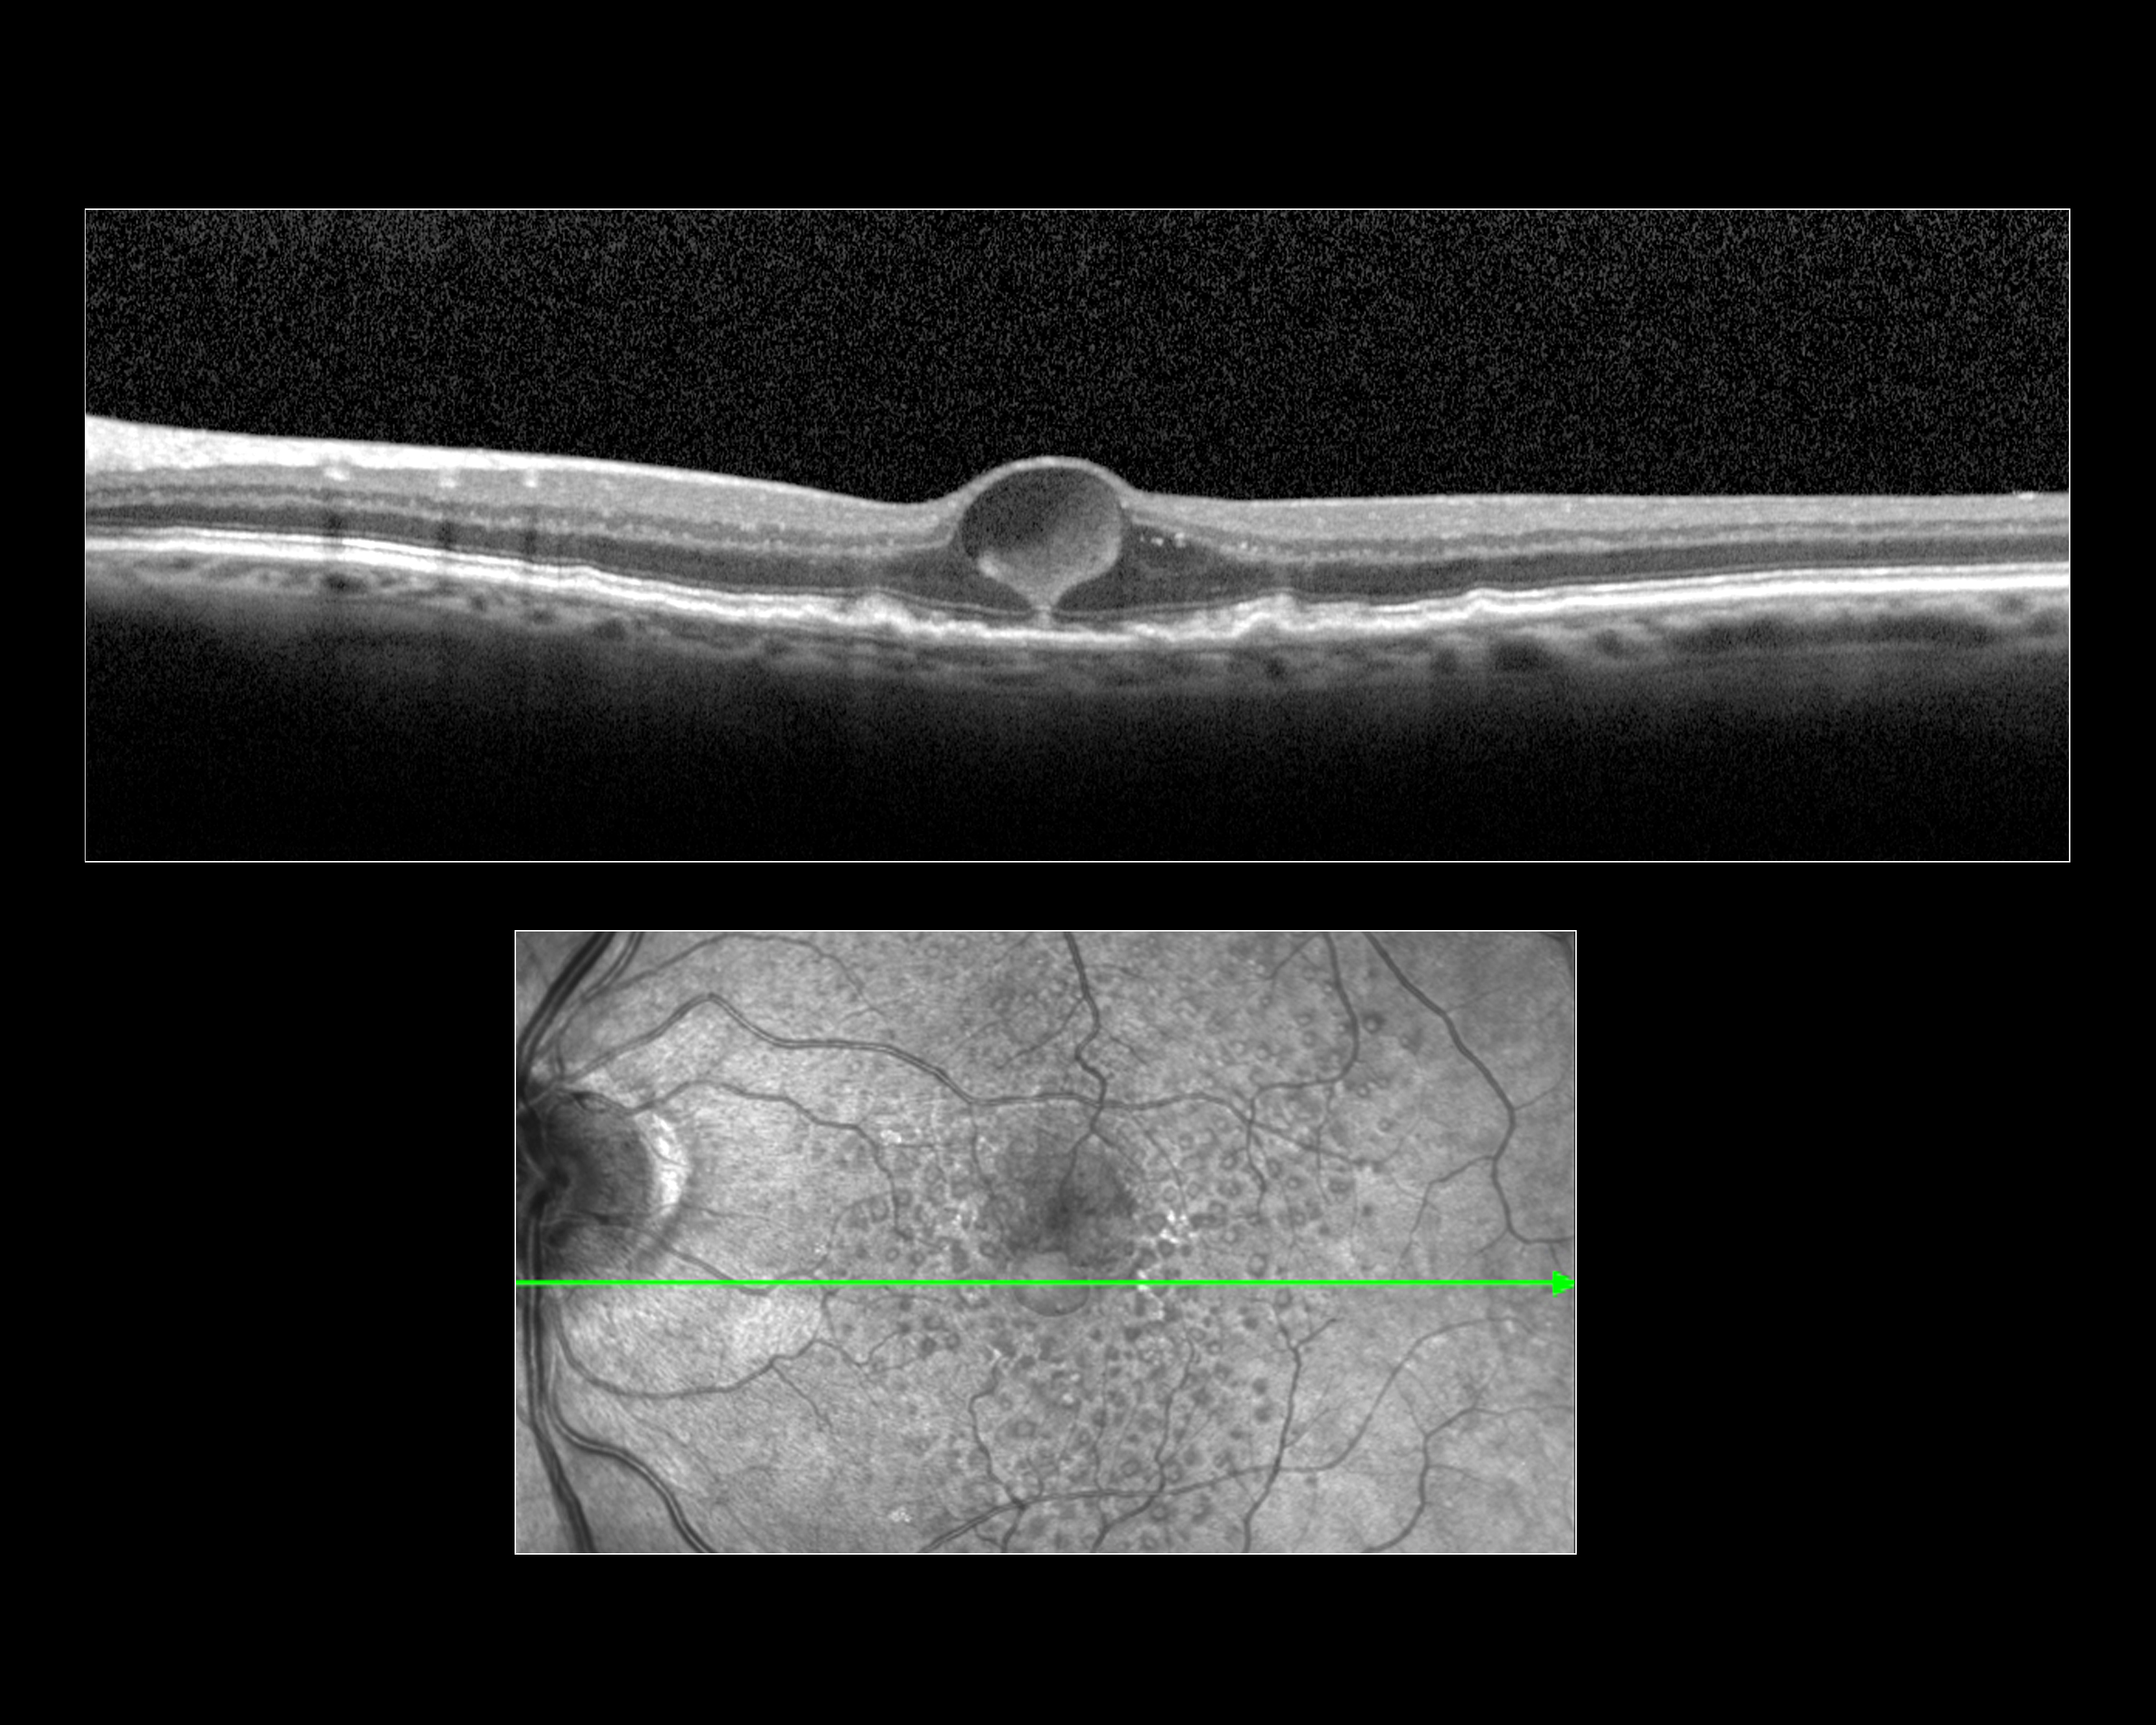

Macular Cyst Presented by Megan Walsh, CRA, OCT-C This photograph received First Place, Ocular Coherence Tomography in the 2025 OPS Scientific Exhibit. Filed Under Retina OPS Photo